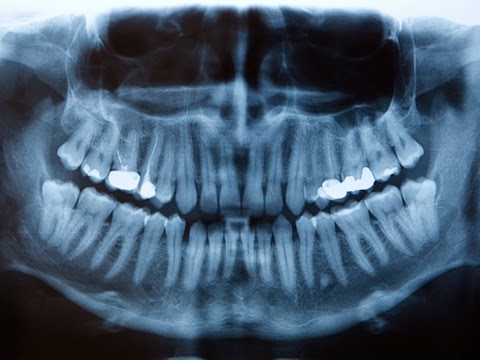

- Check and clean your teeth.

- Take x-rays.

Problems with teeth are the most common. Permanent teeth may be slow to come in and may look different from normal teeth. Teeth may fall out. The dentist will check your child’s jaws for any growth problems.

Before chemotherapy begins, take your child to a dentist. The dentist will check your child’s mouth carefully and pull loose teeth or those that may become loose during treatment. Ask the dentist or hygienist what you can do to help your child with mouth care.